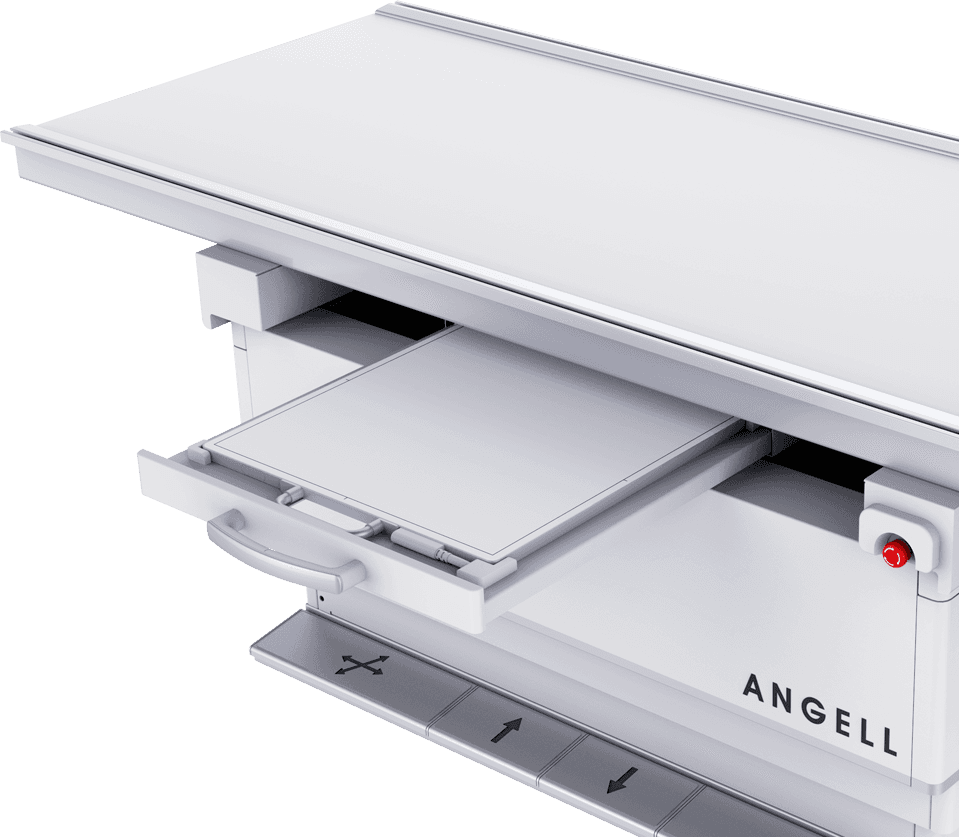

电动升降床

超大行程运动范围,灵活应对儿童、老人、外伤患者上下床。

配备嵌入式感应解锁系统,轻松调节床高并有效避免患者误触。

动静双板自由切换

动态平板+静态平板双板配置,可实现毫秒级选板切换。

配合手自一体悬吊式机械运动系统,多体位拍摄转换轻松自如,大幅提升临床检查效率 -